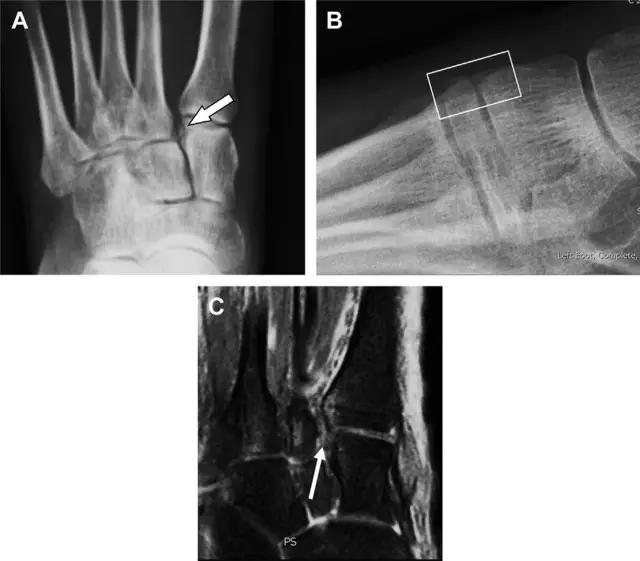

11 Segond 骨折

Segond 骨折是发生在胫骨平台外侧的垂直撕脱性骨折(图 4)。这种骨折在前后位 X 线片上显示最佳。

屈曲位时膝关节受到内旋*力暴**作用,导致皮质骨撕脱性骨折,这种骨折常发生在运动员身上。常引起股骨内髁和胫骨平台后内侧骨挫伤,75%~100% 的患者伴前交叉韧带断裂,33% 的患者伴外侧半月板损伤。

图 4 一位足球运动员的 Segond 骨折

A 正位片示关节线下方胫骨外侧皮质撕脱(箭头)。B MRI 冠状位 T1 加权像示附着于髂胫带的骨折碎片(空箭头)。